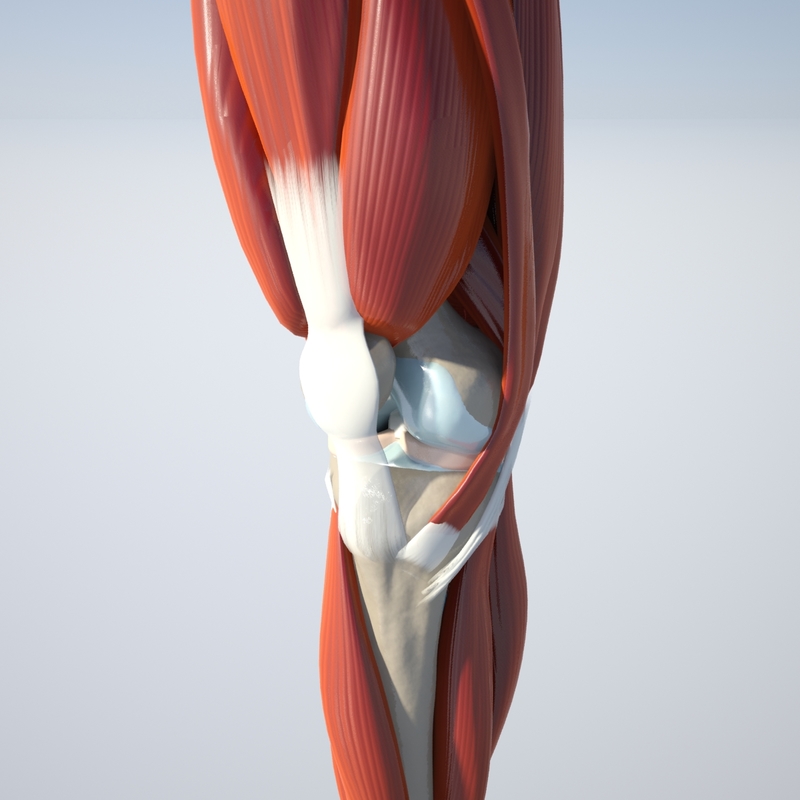

www.turbosquid.comknee turbosquid

www.turbosquid.comknee turbosquid

膝盖3D模型 - TurboSquid 607910

www.turbosquid.comYes, You May Use These For Reference. Edit: 2014-05-05. The Anatomy Is

www.turbosquid.comYes, You May Use These For Reference. Edit: 2014-05-05. The Anatomy Is

Knee Joint 3D Model | CGTrader

www.cgtrader.comknee cgtrader science

www.cgtrader.comknee cgtrader science

Dynamic Knee Model - Modeling Anatomical Accuracy

dynamicdiscdesigns.comFlüssigkeit Im Knie – Heilpraxis

www.nhs.ukThe Knee Joint Anatomy

www.nhs.ukThe Knee Joint Anatomy